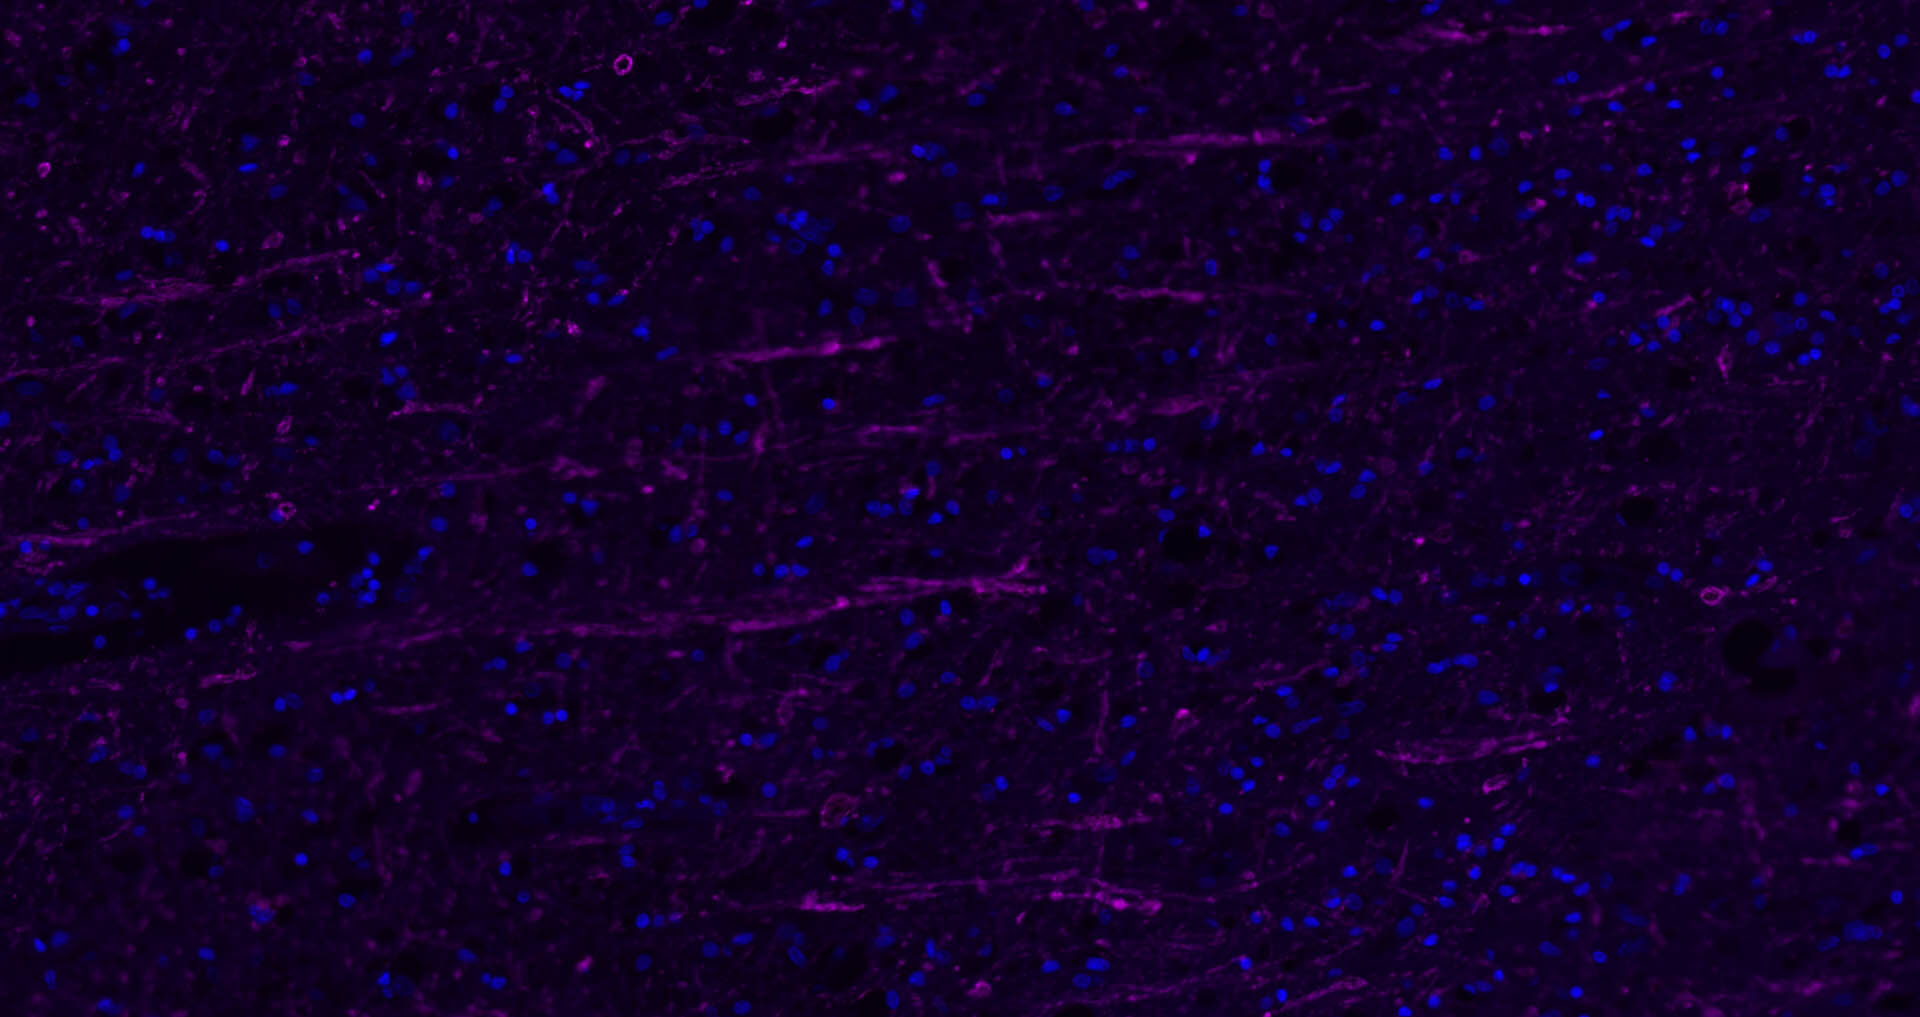

Paraformaldehyde-fixed, paraffin embedded Rat Cerebrum; Antigen retrieval by boiling in sodium citrate buffer (pH6.0) for 15 min; Antibody incubation with NF-L Polyclonal Antibody, Unconjugated (bs-41217R) at 1:200 overnight at 4°C. Followed by conjugated Goat Anti-Rabbit IgG antibody (Purple, bs-0295D-Cy5), DAPI (blue, C02-04002) was used to stain the cell nuclei.